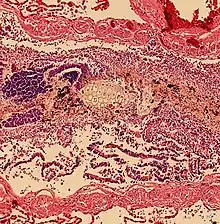

| Upper gastrointestinal series at the level of the esophagus, showing pulmonary aspiration of the radiocontrast agent | |